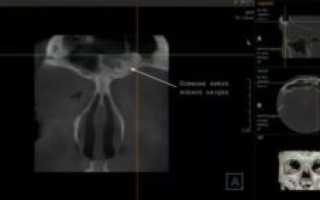

- компьютерная томография (КТ остеомы лобной доли);

При необходимости уточнения диагноза, для выявления окно клеток опухоли в области носа и околоносовых пазух, а также на костях черепа рекомендуется проведение компьютерной томографии.

- Компьютерная диагностика (КТ) выясняет расположение опухоли, размер очага и влияние на соседние структуры.